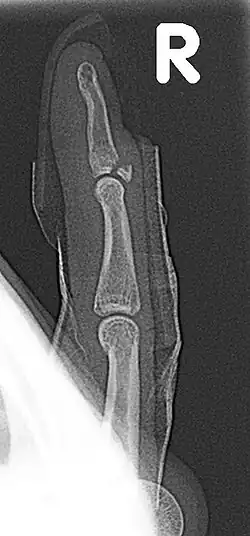

| Fracture of the dorsal base of the distal falange by extensor tendon avulsion (Busch fracture) | |

In medicine a Busch fracture[1] is a type of fracture of the base of the distal phalanx of the fingers, produced by the removal of the bone insertion (avulsion) of the extensor tendon. Without the appropriate treatment, the finger becomes a hammer finger. It would correspond to the group B of the Albertoni classification.[2] It is very common in motorcycle riders and soccer joggers, caused by hyperflexion when the tendon is exercising its maximum tension (the closed hand tightening the clutch lever or the brake lever).[3][4]

A Busch fracture, showing the characteristic mallet finger -

Busch fracture mechanism: because the bit of bone attached to the tendon has broken off, the tendon can't extend the finger tip